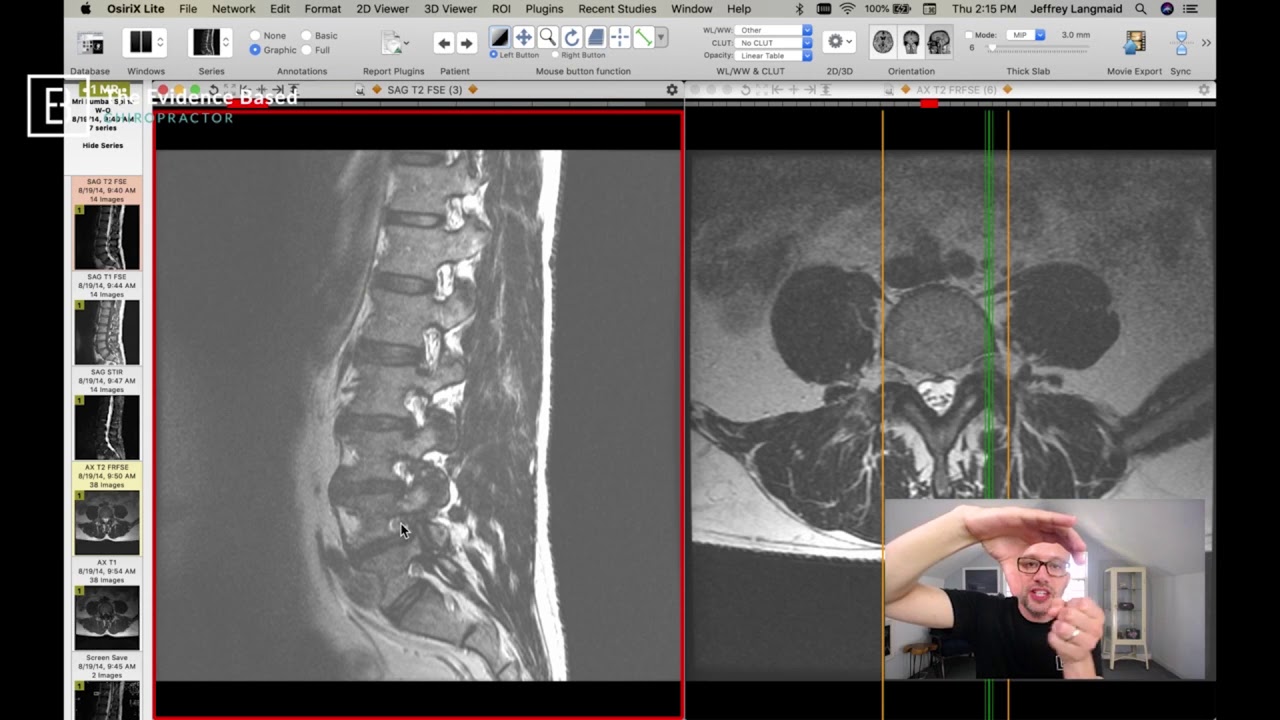

Dr. Gillard Lectures on Lumbar Disc Herniation / Protrusion. Part I of II

Автор: Douglas Gillard, DC, Professor of Clinical Science

In this video, Dr. Gillard, a world-renowned expert in lumbar spine pathology, presents an entry-level lecture on lumbar disc herniation. Although a very brief description of the lumbar spine anatomy and how to read your lumbar MRI is given, the doctor recommends viewing his other YouTube videos on the subjects which can be found at the following links: